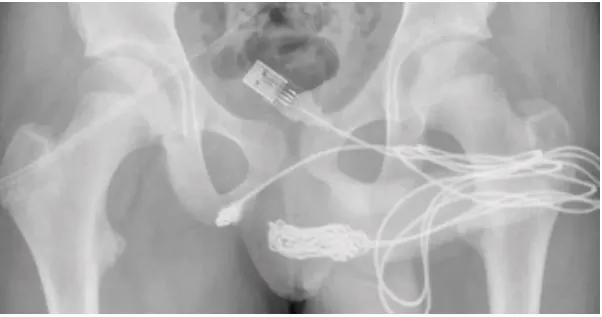

REDACCIÓN INTERNACIONAL.-Un joven de Reino Unido fue operado de emergencia tras introducirse en el pene un cable USB con la idea de saber cuánto medía su órgano reproductor.

El chico de unos 15 años de edad, contó a los doctores que se había insertado el cable en la uretra para medir la longitud de su pene “por curiosidad sexual” y había intentado sacarlo por sí mismo, debido a la imposibilidad para “desenredar” el cable de unos 10 centímetros.